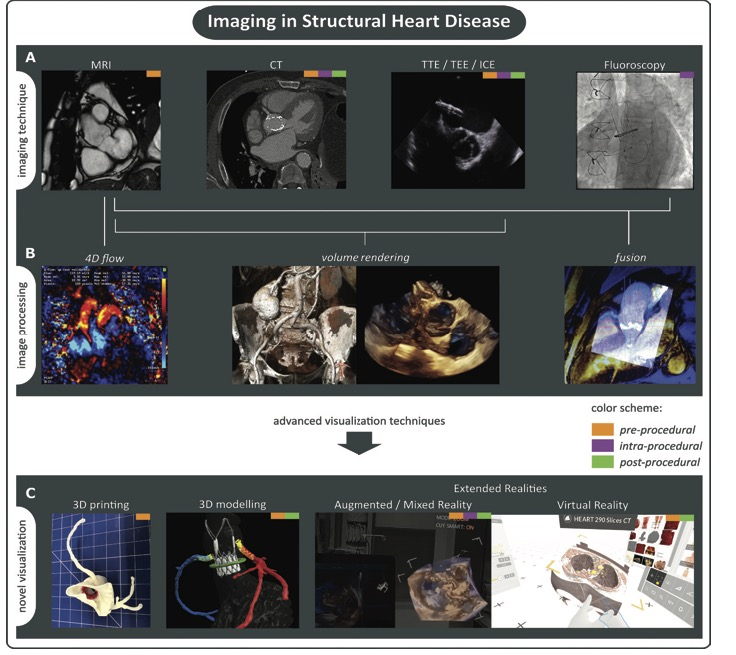

在结构性心脏病患者的介入手术治疗流程(术前评估、术中指导和术后随访)中,综合使用上述检查方法的案例如下图所示:

A: 目前,医生使用的主要影像检查

B: 不同的成像方法可以经过后处理增强显示或者实现不同成像技术的融合显示。

C:数据和后处理图像的临床可视化,如虚拟现实(virtual reality,VR)、增强现实(augmented reality,AR)和/或混合现实(mixed reality)、基于分割的三维建模(segmentation-based 3D modelling)和三维打印(3D printing)。